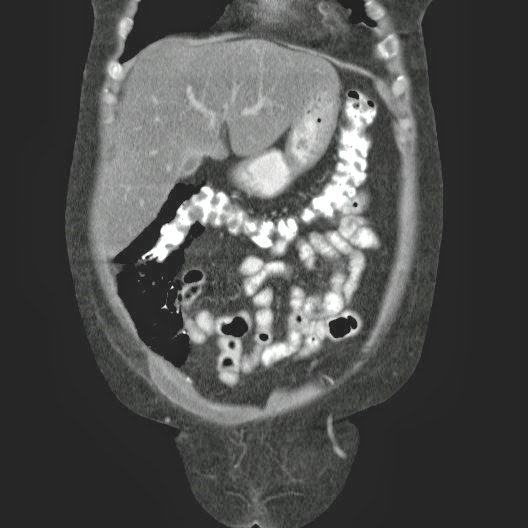

Caso Interesante #4

Adulto masculino, 1 semana de fiebre y malestar general.

¿Dónde esta ubicado el hallazgo?